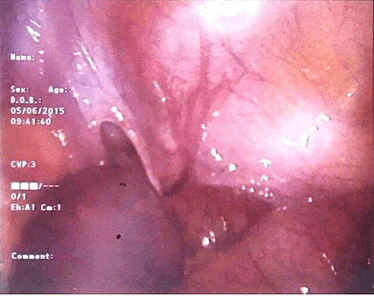

A 73-year-old woman with no prior surgical history presented to the emergency department with a four-day history of abdominal distension, bilious vomiting and not opening her bowels. On physical examination her abdomen was markedly distended, but soft, non-tender with tinkling bowel sounds. Rectal examination revealed no abnormalities. Laboratory findings showed raised inflammatory markers: CRP 123 mg/l and plain film radiography revealed dilated small bowel loops (Figure 1). A CT scan of abdomen and pelvis was subsequently performed which showed dilated small bowel with a transition point in the distal ileum with no definite cause of obstruction identified. Initially, she was managed conservatively with nasogastric tube decompression, intravenous antibiotics and fluids with little improvement of her symptoms. Therefore a diagnostic laparoscopy was undertaken. Intraoperative findings revealed internal herniation of distal ileum through a 3x3 cm defect in the broad ligament of the uterus (Figure 2) and (Figure 3). The small bowel had no evidence of ischaemia therefore was simply reduced and the defect of the broad ligament was closed with 2–0 vicryl stitches (Figure 4). Postoperatively her symptoms completely resolved leading to her discharge after three days.

Figure 2: Laparoscopic image showing intestinal herniation through a defect in the broad ligament of the uterus.

Figure 3: Laparoscopic image showing the Type 1, fenestra, 3x3 cm defect in the broad ligament of the uterus.

The second was devised in 1986 by Cilley which classified broad ligament hernias into three main categories based on the location of the defect within the broad ligament. Type 1 defects are the most common and occur in the mesometrium, which contains the greater section of the broad ligament. Type 2: interrupt the mesosalpinx and the mesovarium. Type 3: arise within the centre of the round ligament [7]. The patient in the case described above had a Type 1, fenestra broad ligament defect.